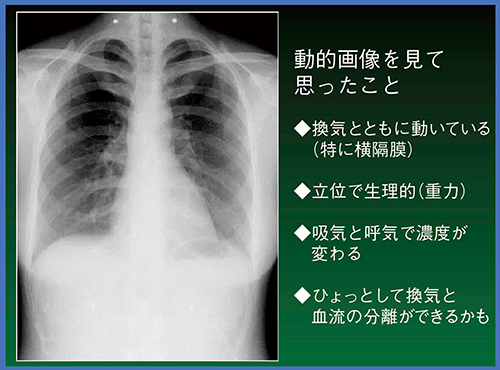

コニカミノルタ社からX線動態画像を提示された際,(1) 換気とともに心臓の拍動や横隔膜の運動が描出できる,(2) 立位で胸部の動態を観察できるため,CTやMRIでは困難な生理学的情報を得られる,(3) 吸気と呼気での濃度変化の情報を得られる,(4) 換気や血流を分離して観察・評価できる可能性がある,と考えられた(図4)。

図4 X線動態画像の可能性